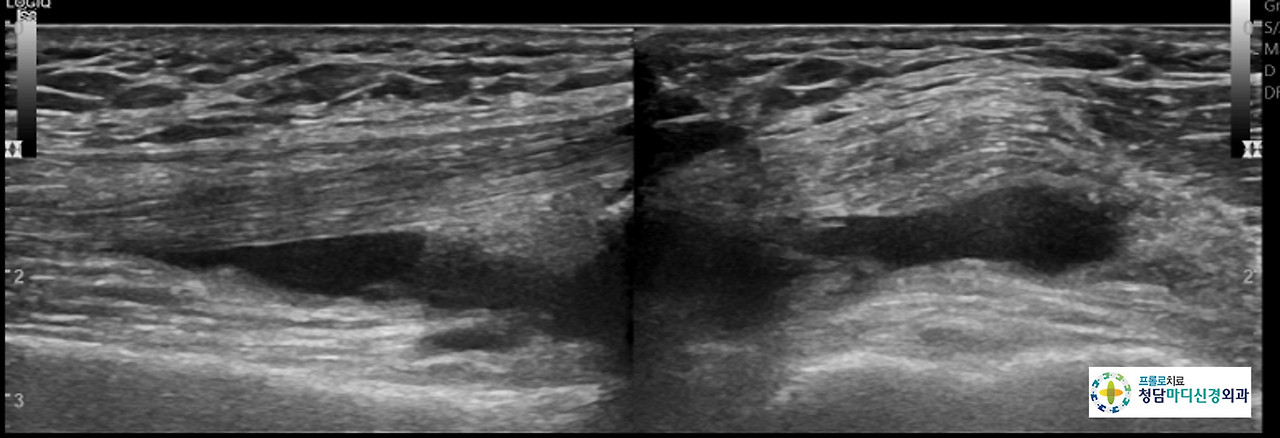

0516(6).jpg 프롤로치료후 초음파 영상: 관절내의 삼출액의 없어짐

앞서 말씀드린 환자분은 4주간격으로 3회의 치료를 받고, 3개월후에 다시 내원하여 증상의 여부를 확인하였습니다. 환자분은 통증이 VAS 10 에서 VAS 1~0 으로 줄어들었고, 무릎의 부기도 없어졌다고 좋아하시면서, 치료후기를 작성하여 주셨습니다. 프롤로치료는 연세가 많으셔도 의외로 좋은 효과를 보는 분들이 많으십니다. 나이와 관계없이 프롤로치료를 해보실 것을 권해드립니다.